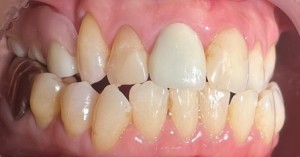

4日目 ジルコニアクラウンを装着し、ノンクラスプデンチャーの型取りを行いました。

5日目 ノンクラスプデンチャーを調整しました。

患者様の希望である『なるべく歯を削る量が少なく、インプラント以外の方法』で治療できたことに、大変満足されていました。